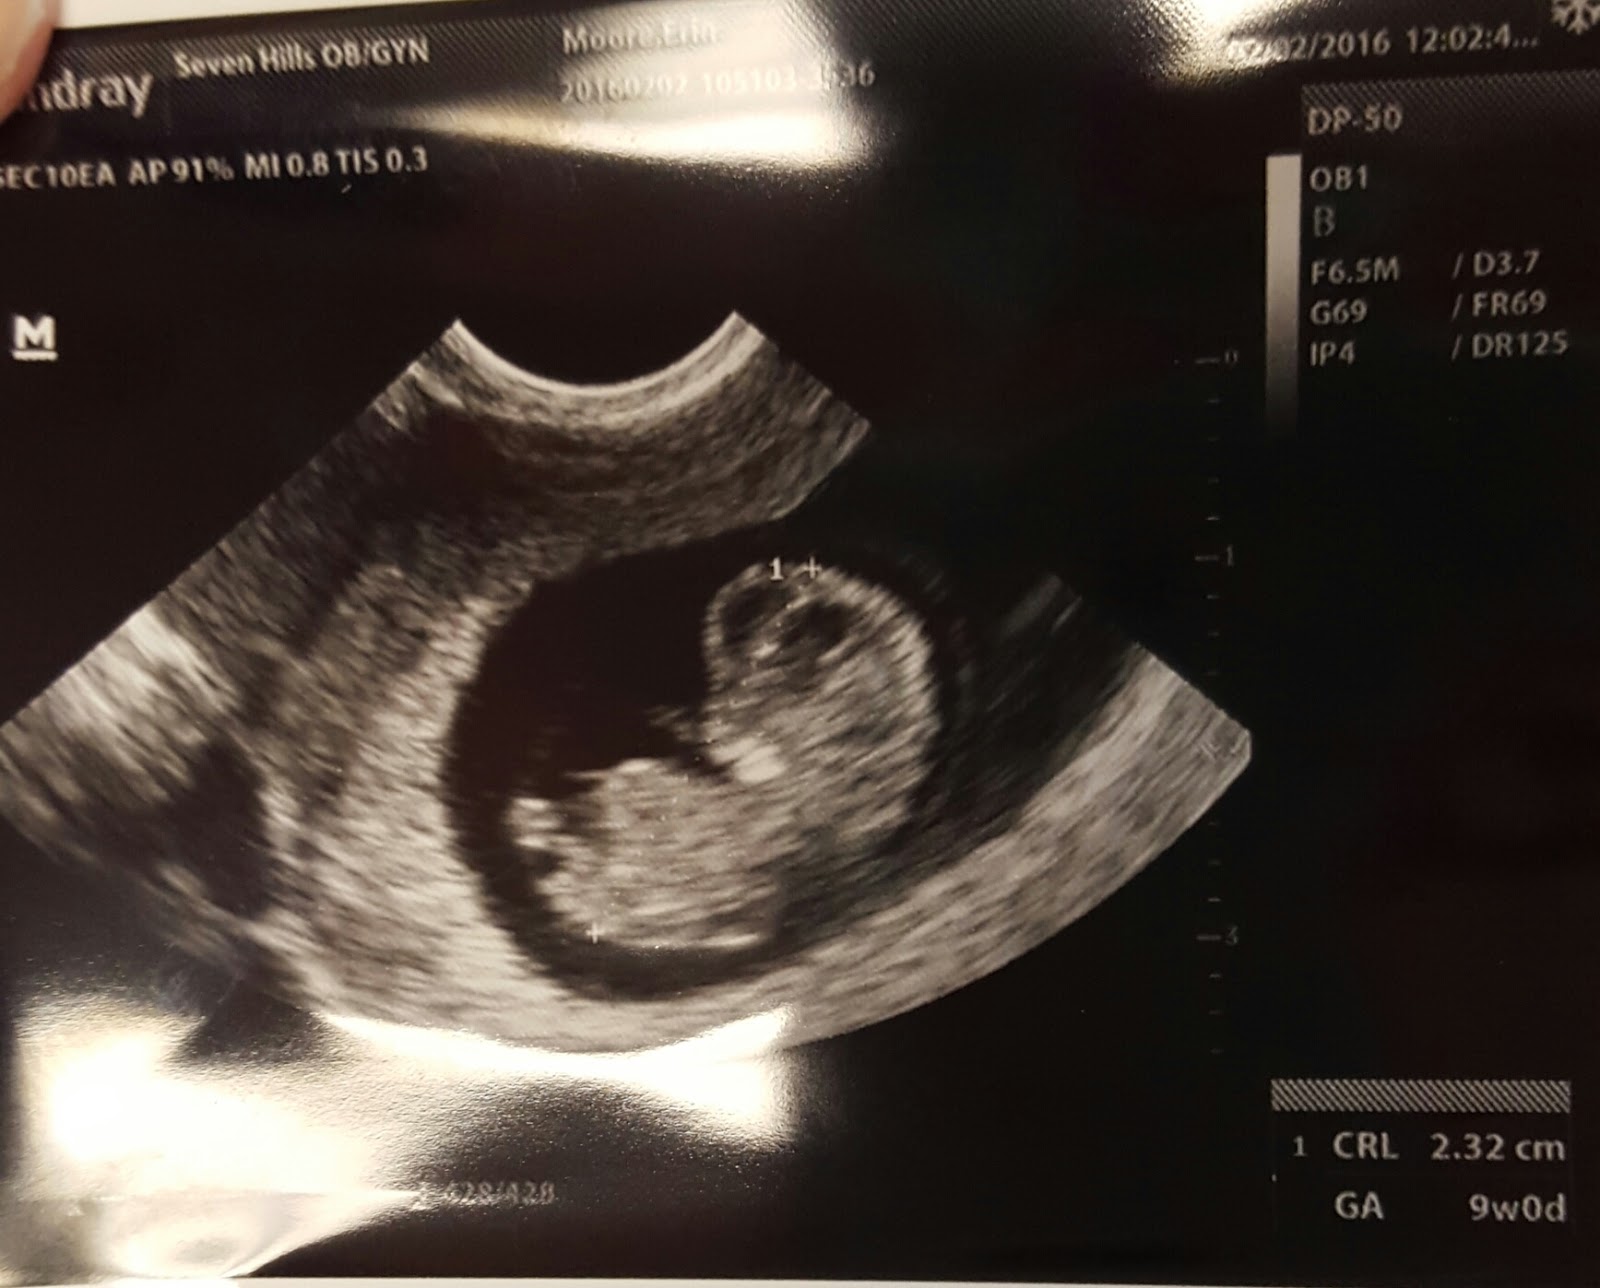

Today we have reached 9 weeks 3 days! We have already seen so many milestones, for us, anyway! With each appointment, we go in with excitement, fear, hope, and anxiety. My doctor is amazing and will see me anytime I need to. I already have many more ultrasound pictures than most do at only 9 weeks! I have welcomed all the sickness and fatigue and have been taking short and easy days at work. Maybe we’re crazy, but every time I throw up, Jordan and I grin and giggle- giddy with excitement that symptoms are still around. In fact, between week 6 and 7, I started feeling pretty good and the nausea had faded quite a bit. I got so nervous that I called the doctor and she saw me the next day, did an ultrasound, and everything was fine! I have been seeing her every 1.5-2 weeks so far. My next appointment is with the Maternal Fetal Specialist (the high risk doctor I have been referring to) and that is not until February 22! My longest wait in between appointments yet! As long as there are no reasons for concern between now and then, I am going to try not to worry myself enough to have to schedule another ultrasound! Doctor suggested we order a fetal heart doppler, so that has been ordered and we’re waiting for it to arrive. I know it is too early for us to use right now, but maybe before the 22nd we will be able to hear the heart beat at home. But, I have read they can be tricky, so I am telling myself that if we don’t hear the heartbeat at home, it is probably because I am using the machine wrong!

Since we had already taken off work 3 days for the funeral, Jordan didn’t feel like he should ask off again, so I took our moms with me to the doctor appointment yesterday. An ultrasound wasn’t planned, but I asked for one so they could see. It was going to be an additional charge, but I had some spotting yesterday morning, so that gave a medical “reason” for an ultrasound and I didn’t have to pay any extra! I have read a lot about women on lovenox having some spotting throughout the pregnancy. I also had slight change in progesterone pills the night before, and I have been told any change in that could cause some spotting. I still don’t like to see that- but was comforted to see that all was fine! While the moms were there, the baby moved for us during the ultrasound! It was so exciting to see the movement, the growth, and the development! We even got a video of the baby moving! -see below-